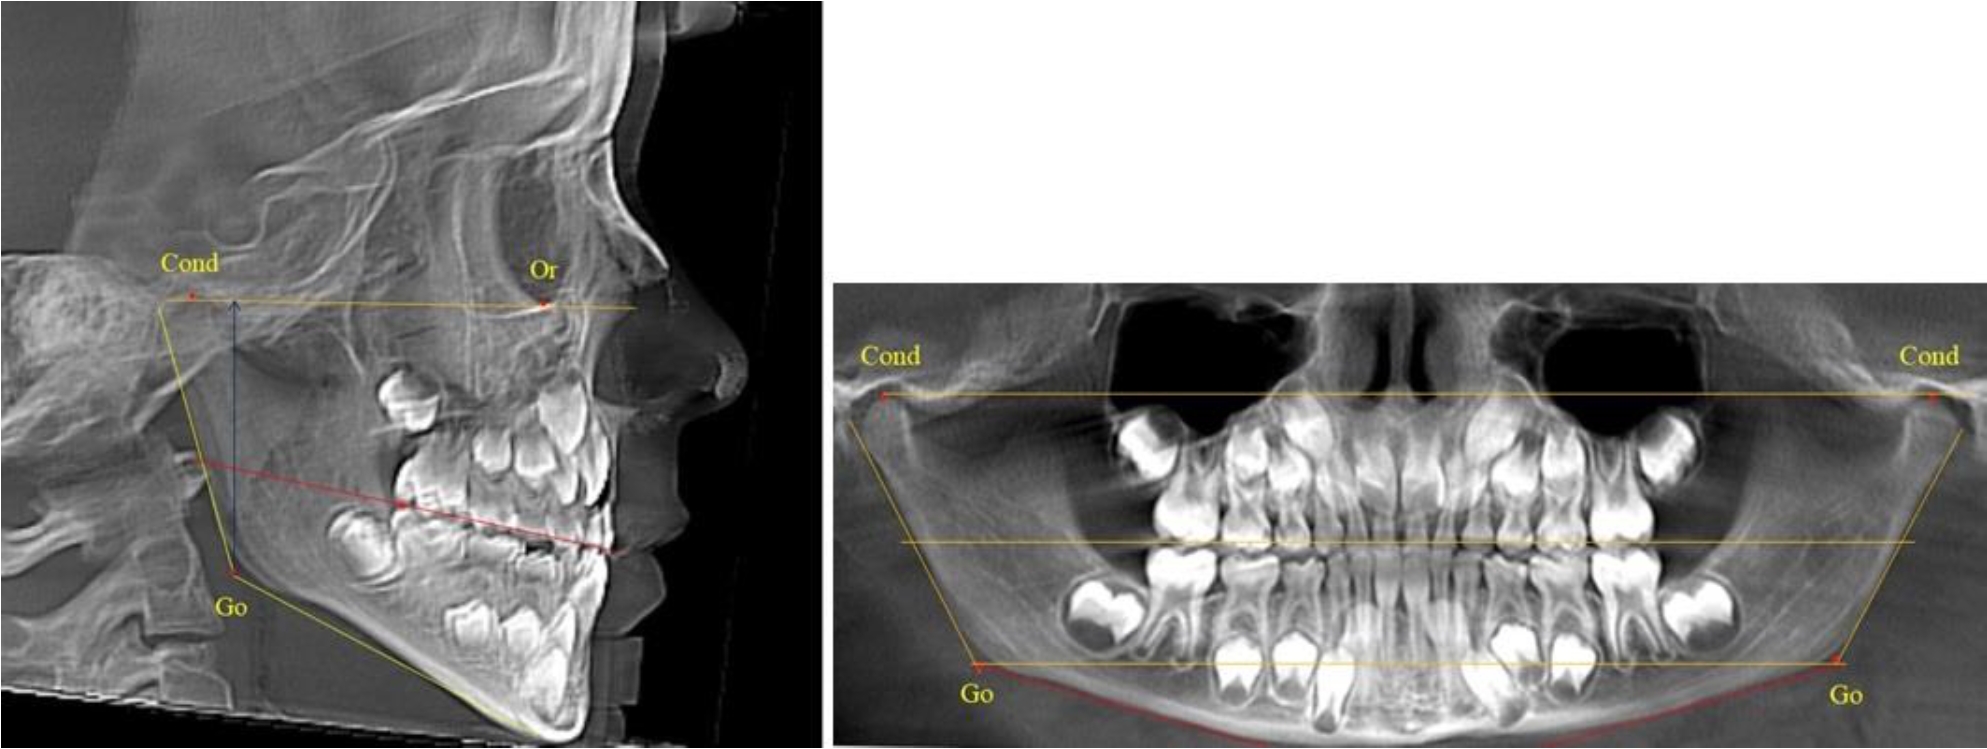

В 1-й группе были проанализированы 7 телерентгенограмм и 7 ортопантомограмм, что составило (6,60 ± 2,41) % от числа изученных рентгенограмм. На всех парах рентгенограмм угол нижней челюсти, измеренный на телерентгенограмме, соответствовал углу, полученному при построении угла на ортопантомограмме. Окклюзионная линия практически однотипно делила ветвь на два отдела (рис. 1).

Как на ортопантомограмме, так и на телерентгенограмме высота ветви у детей в периоде сформированного прикуса молочных зубов составляла (42,21 ± 2,48) мм. При этом высота верхней окклюзионно-суставной части была (22,57 ± 1,46) мм, а нижней – (19,64 ± 1,54) мм.

Учитывая вариабельность абсолютных величин, определи относительные показатели соразмерности частей ветви нижней челюсти. Так, отношение высоты верхней части ветви к нижней в среднем составляло 1,15 ± 0,13. Отношение общей высоты ветви к верхней ее части составляло 1,87 ± 0,14, а отношение общей высоты ветви к нижней ее части было 2,14 ± 0,16 и достоверных различий по относительному показателю отношения всей высоты к верхней и нижней челюсти нами не отмечено (р ˃ 0,05). При этом визуально обе части выглядели примерно равноразмерными.

В 5-й группе были проанализированы 14 комплектов рентгенограмм, что составило (13,21 ± 3,29) % от общего числа. На всех рентгенограммах отмечен очередной этап подъема высоты прикуса, обусловленный прорезыванием вторых постоянных моляров. Окклюзионная линия делила ветвь на два отдела (рис. 5).

Рис. 5. ТРГ и ОПТГ пациента после смены молочных зубов и прорезывания вторых постоянных моляров

Высота ветви у детей 5-й группы составляла (62,87 ± 3,62) мм, что было достоверно больше, чем у детей других групп (р ˂ 0,05). При этом высота верхней окклюзионно-суставной части была (40,23 ± 2,01) мм, а нижней – (22,64 ± 1,78) мм. Высота верхней части была вдвое больше нижней, что и определяло особенности соразмерности частей ветви нижней челюсти в анализируемый возрастной период.

Относительные показатели соразмерности частей ветви нижней челюсти показали, что отношение высоты верхней части ветви к нижней в среднем составляло 1,78 ± 0,18. Отношение общей высоты ветви к верхней ее части составляло 1,56 ± 0,12, а отношение общей высоты ветви к нижней ее части было 2,78 ± 0,14, что и определяло особенности соразмерности частей ветви нижней челюсти в анализируемый возрастной период.